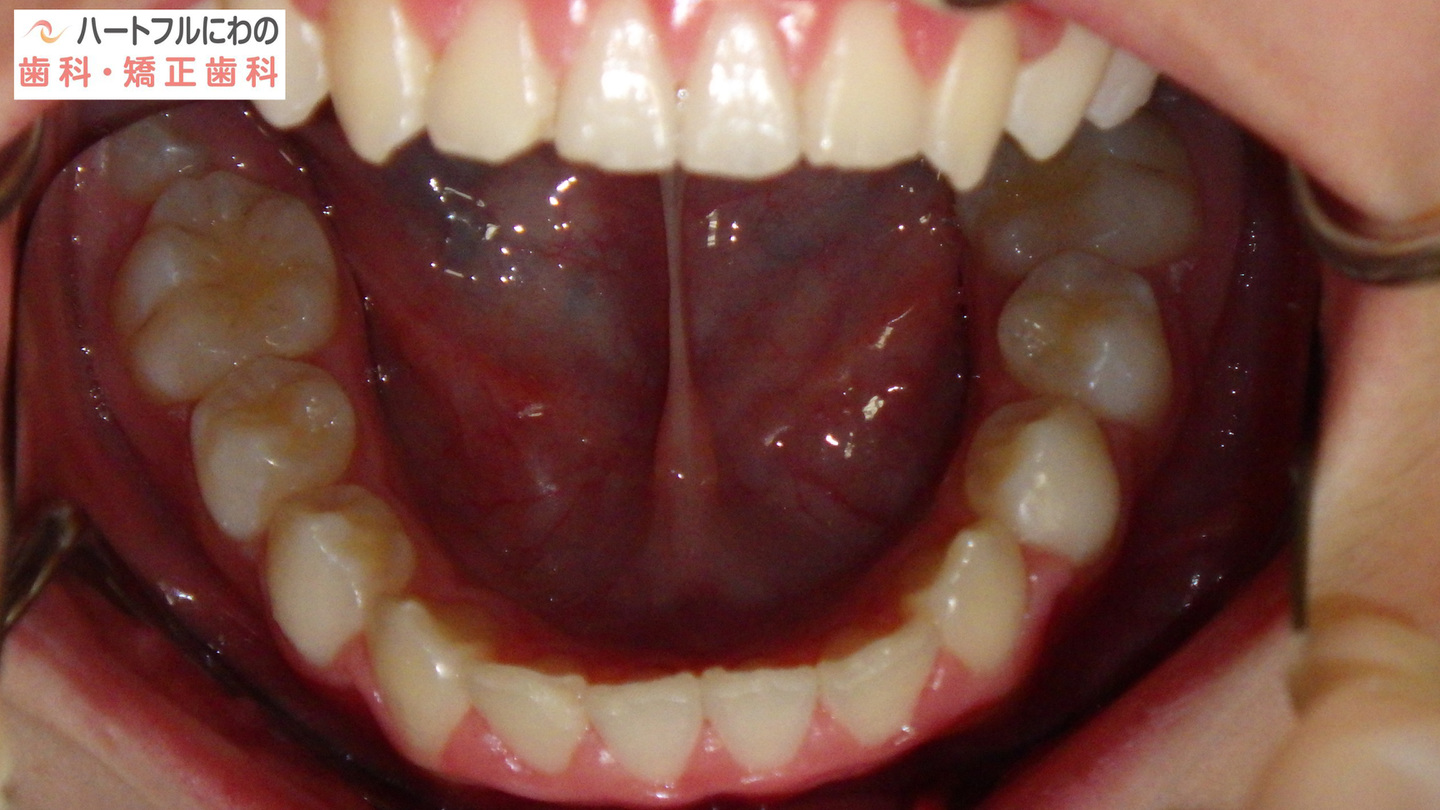

お口の中を拝見すると、上下の叢生(いわゆるガタガタ、乱ぐい)がみられ、多数の虫歯と歯肉炎がみられました。上唇小帯(上唇のすじ)の問題もありました。口呼吸で口腔内が乾燥すると通常の何倍も歯垢が付きやすくなり、虫歯や歯肉炎が頻発します。口呼吸の強い子は重なっている部分のかみ合わせが深い(下の歯がほとんどみえない)のもよく見られる特徴です。

その間に食事指導も含め、虫歯や歯周炎の管理も行います。このお子さんは炭酸を含む清涼飲料水が好物でその指導に苦労しましたが、初診時以降は虫歯の発症なく、思春期性の歯肉炎も軽度ですんでいます。

奥歯と前歯の前後的位置関係は大きく改善し、正常になりました。

細かい部分の修正や緊密な咬み合わせを作るための二期治療(仕上げ)は一年以内で終了予定です。